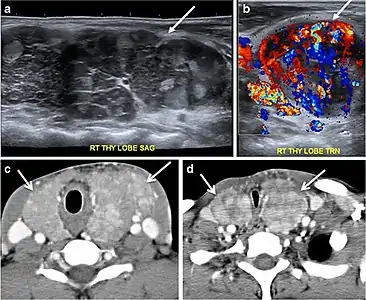

Fig. 14. A 19-year-old male patient known to have multi-nodular goiter and FNA, showing underlying Hashimoto's thyroiditis. a, b Sagittal and transverse greyscale and colour Doppler ultrasound of the neck demonstrate a hypoechoic enlarged right thyroid lobe with small hyperechoic regenerative nodules and marked hypervascularity (white arrows). c, d Enhanced axial CT scan images of the neck demonstrate a heterogeneously enhancing and enlarged thyroid gland, left more than right lobe, and the trachea is markedly narrowed.[1]